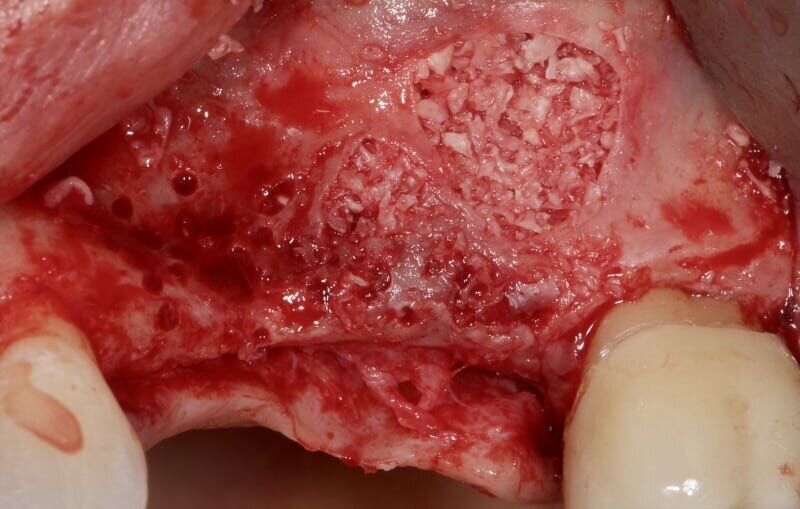

In fase preoperatoria è stato prescritto aerosol (2 volte al giorno per 7 giorni) con beclometasone dipropionato (Clenil 0,8 mg/2 ml) e soluzione ipertonica (Libenar 22g/l) a partire da 7 giorni prima dell’intervento e antibiotico (Amoxicillina 1 g - ogni 12 ore a partire dal giorno precedente l’intervento per 6 giorni). È stato eseguito il rialzo di seno mascellare del secondo quadrante per via laterale abbinato a una contestuale tecnica di GBR/Guided Bone Regeneration (Figg. 4-6). Come sostituto osseo è stato utilizzato lo xenoinnesto bovino Re-Bone® (Ubgen, Padova, Italy) da 1 g con granuli cortico-spongiosi 0,25-1 mm (Figg. 7, 8, 11). Questa metodica è stata abbinata a Shelter ® membrana in pericardio bovino (Ubgen, Padova, Italy) fissata poi con appositi pins ritentivi (Figg. 12, 14, 15). Terminata la tecnica di GBR, sono stati suturati i lembi (Vicryl, 4/0, Johnson & Johnson Int.) (Fig. 16).